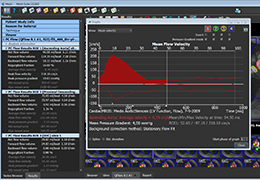

ANYTHINK 经导管主动脉瓣膜置换术分析系统